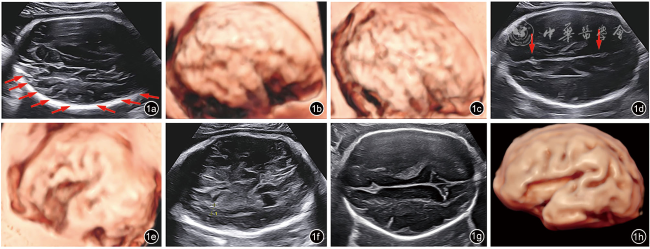

图2 孕30周胎儿多小脑回畸形(双侧)的MRI表现。图a可见外侧裂形态可;图b、c可见脑沟回增多,见众多浅细脑沟

孕妇35岁,孕3产1,夫妻均体健,非近亲结婚,否认孕前、孕期毒物与放射线接触史,否认家族遗传病史。2023年3月开始于深圳市妇幼保健院规律产检。自然受孕,经早孕期孕8周超声核对末次月经及预产期无误。停经12周胎儿超声提示:胎儿大小相当于13+4周,颈项透明层厚度(nuchal translucency,NT)1.7 mm,胎儿鼻骨可见,心脏声像改变提示右位主动脉弓。经遗传学咨询后,于16+2周行羊膜腔穿刺,采集胎儿羊水进行染色体核型分析+染色体微阵列分析,结果均未见异常。孕22+1周行Ⅲ级超声检查:胎儿大小相当于25+1周。胎儿右位主动脉弓,左锁骨下动脉迷走,左位动脉导管,其与左锁骨下动脉相连,动脉导管、左锁骨下动脉及主动脉弓三者形成“U”形血管环,局部气管受压,受压段宽约0.17 cm,其上段宽约0.27 cm。胎儿头围位于均数+3.49标准差,腹围位于均数+3.02标准差,体重位于第99.95百分位[参考美国国家儿童健康与人类发展研究所(National Institute of Child Health and Human Development,NICHD)曲线],胎儿左侧侧脑室宽约0.96 cm。胎儿永久性右脐静脉。由于胎儿超声出现新表型“大头畸形”及“过度生长”,原有羊水DNA进一步检测甲基化特异性多重连接探针项目排查Beckwith-Wiedemann综合征,结果为阴性;孕妇拒绝同时行家系全外显子组测序(whole exome sequencing,WES)。孕26周孕妇诊断为“妊娠期糖尿病”。孕26+1周复查超声提示胎儿头围进行性增大:胎儿头围位于均数+4.96标准差,腹围位于均数+2.88标准差,体重位于第99.95百分位,胎儿左侧侧脑室宽约0.92 cm。再次告知原有羊水检测项目的局限性,夫妻知情同意原有羊水DNA进一步行WES,结果提示,在PIK3CA基因上检出与胎儿临床表型相符的可能致病变异:NM_006218.4:c.1346C>T(p.Pro449Leu)杂合变异,经夫妻双方外周血验证均为野生型,为新发变异。孕妇于孕29+6周再次复查超声提示:胎儿大小相当于35+2周,胎儿头围位于均数+6.2标准差,胎儿颅脑声像改变:巨头畸形、多小脑回(图1a~1c)、外侧裂及顶枕沟浅(图1d、1e),脑实质分层明显(图1f)、左侧脑室宽1.3 cm。胎儿右位主动脉弓,左锁骨下动脉迷走并“U”形血管环形成。胎儿永久右脐静脉。孕30周行胎儿头颅MRI检查提示(图2):胎儿巨头,多小脑回畸形,双侧脑室增宽,胎儿额枕径位于均值+4标准差以上水平,双顶径、骨双顶径、胼胝体长度位于均值+3标准差以上水平,小脑蚓部前后径位于均值+2标准差以上水平,小脑蚓部高度位于均值+7标准差以上水平。根据多次超声及MRI结果,胎儿可诊断为脑皮质发育畸形(malformations of cortical development,MCD),综合基因检测结果及产前影像学表现,提示胎儿预后不良,孕妇及家属知情并于孕31+3周引产,胎儿出生体重2940 g,头围34 cm,胸围33 cm,腹围33 cm,身长49 cm,外观未见明显异常,未行胎儿尸解。本病例报道通过深圳市妇幼保健院伦理委员会批准(批件号:KYYS-2025-039)。